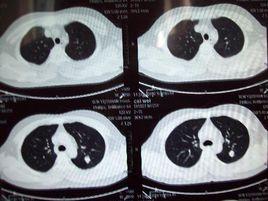

正常值 臨床意義 注意事項 檢查過程 相關疾病胸部的CT是通過X線計算機體層攝影(CT)對胸部進行檢查的一種方法。正常胸部CT層面較多,每一層面結構所表現的圖像不同。如果無異常,醫生會在在報告單中寫...

意義CT(computed tomography)是以電子計算機輔助形成體層二維像的意思。是70年代開始套用於臨床的一種新的成像技術,成像能量使用穿透力很強...